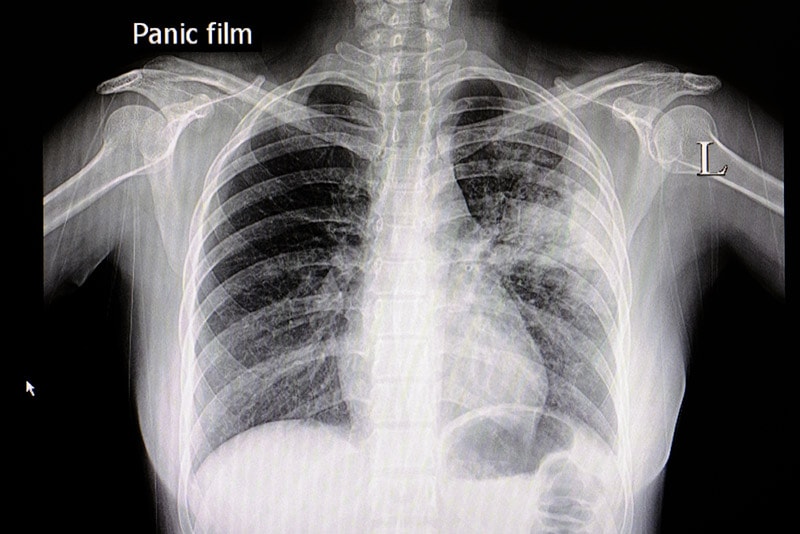

#пневмония

За сутки ещё пять казахстанцев умерли из-за пневмонии с признаками коронавирусной инфекции

20 человек скончались за сутки от коронавируса и пневмонии в РК

Ещё двое казахстанцев умерли из-за пневмонии с признаками COVID-19

В Казахстане за сутки от коронавируса и пневмонии умерли 17 человек

В РК более 20 человек скончались от коронавируса и пневмонии

Сколько человек скончались от коронавируса и пневмонии за сутки в РК

Сколько человек скончались от коронавируса и пневмонии за сутки в РК